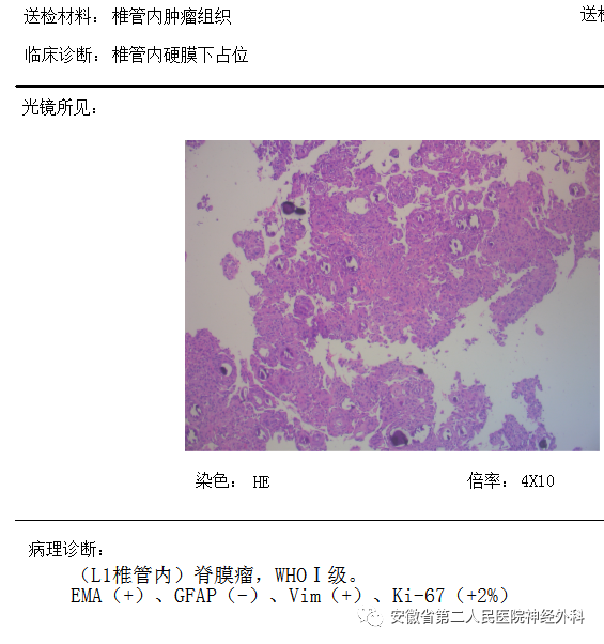

术后病理